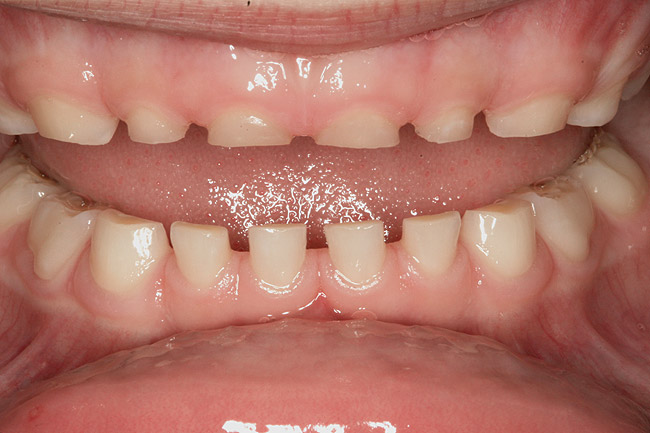

(3.) Three-year-old with a history of snoring, bruxing, and thumbsucking. Her father and brother were both diagnosed with OSA.

Figure 3

(4.) Patient presents bilateral crossbite and significant attrition. Father assists in retraction.

Figure 4